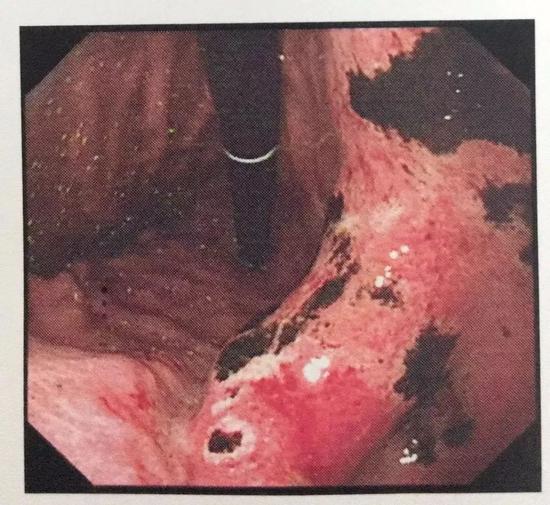

|  麻辣与甜铿锵地刺激着味蕾 极具酸爽的调味料在齿间游走 极具穿透力的香与辣咸与鲜 回荡撞击久久不散 舔舔嘴角的辣油 噬骨销魂 …… 凭借低廉的价格,简单粗暴的口感,支配了两代祖国花朵,至今仍有拥粉无数,垃圾食品界辣条称第二,没sei敢称第一。  壹 一包半网红辣条下肚 武汉小伙整个胃部烂了 辣条,作为一种带有童年记忆的食物,就这样轻易地被人承包了。但因吃辣条,无数人进了医院。 2019年3月,23岁的小张刷短视频时看到一款"网红辣条",网友留言都说吃出了儿时的回忆。小张当时就心动了,嘴馋的他便在网上搜寻同款,正好看到有商家在做活动,便花15块钱一次性买了4袋,一袋125g。  前几天,小张下班吃完晚饭后,他拆开辣条大快朵颐地吃了起来,越吃越过瘾,完全停不下嘴。直到一包半下肚后,小张突然感觉到"烧胃"才停下来。 没想到这之后小张一晚上感觉腹痛、烧心难忍,于是第二天一大清早他就赶往医院。 在无痛胃镜下,清晰显示小张整个胃部满布大片状糜烂和出血病变,还有很多溃疡形成的黑痂附着,为急性胃黏膜病变,损伤程度较重。  这不是第一起类似案例。 2017年11月25日,11岁的四川女孩玲玲,对校外五毛钱一袋的辣条特别情有独钟。在一年多的时间里,她每天至少要吃2袋,多则达到5、6袋。 后来玲玲出现严重腹泻和腹痛,每天腹泻10多次,体重减轻20多斤。父母最初以为只是简单肠炎,多次治疗无效后,最终被确证为罕见的"克罗恩病"。  这种病最大的特点就是没办法根治。这意味着,她小小年纪,就要忍受常年与腹绞痛、胃胀气等病痛为伴的生活。 贰 "五毛"辣条的脏 你想象不到 辣条,真的很脏吗? 我们先来看一份专业测评:  大肠菌群超标,一不小心吃了shǐ 辣条带有大肠菌群是啥意思?意思是,辣条受到了粪便污染…… 成年人每克大便中约含大肠菌群108MPN,你可以简单算一算,然后自行领会你吃进去多少…   菌落总数超标29倍,多大仇多大怨! 有点食品安全常识的同学都知道,菌落总数直接反映食物的卫生状况,虽然菌不一定都致病,但几十万菌落……你造吗,马桶水中的菌落总数大概也就48000CFU/g。  这只是评测的一部分。回想前几日,央视曝光了几家辣条厂商生产的全过程: 记者在一片田野中,找到了包名叫"虾扯蛋"辣条的生产公司。  没有经过任何消毒措施,就进入了生产车间。刚进入,浓重的辣条味就扑面而来。地面上,满地粉尘和油污搅在一起,搅拌桶上满是油污。  水池里也到处都是厚厚的油垢,桶里还装着难以名状的不明物体:  除了面粉,就是各种调味用的添加剂和着色剂。  记者又来到另一家辣条生产厂家,走进一看,地面上堆满了各种辣条——    据《新京报》报道盘点,2015年~2017年5月,国家及各地方食药监局的抽检数据共计通报了180起问题辣条。 在通报的180起食品安全问题中,食品添加剂不合格是主要原因。 微生物超标占40.51%,同时仍存在添加剂超标、菌落总数超标等多项问题。 叁 别拿生命过嘴瘾 不正规生产的辣条的危害,最少也有以下四种。 1、诱发慢性疾病、肥胖、高血压 辣条,一般采用油浸或油炸的方式加工成的。因为用油脂进行搭配,再加上配料是各种食品添加剂。 长期食用这类高钠、高糖、高脂的小食品,后果可想而知。  2、致癌 如果不良商家用劣质的过期油脂或反复使用过的地沟油,经常吃用这样油脂制作的辣条,会增加患癌几率。 此外,若商家还违规使用使用工业盐、添加剂等,长时间摄入会出现腹泻、腹痛、心跳加快等,出现急慢性中毒,甚至诱发癌症。  3、便秘 辣条通常是大豆皮、辅以辣椒粉、色素等腌制而成。 辣条吃完后,短时间会刺激汗腺分泌,大汗淋漓,似乎很爽,但是辛辣的辣条吃多了会上火,影响胃肠的蠕动功能,导致便秘。 只能说,真的想吃,至少选择有正规公司和质检达标拿到证书的产品吃。千万别拿生命过嘴瘾。  来源:武汉晚报 |